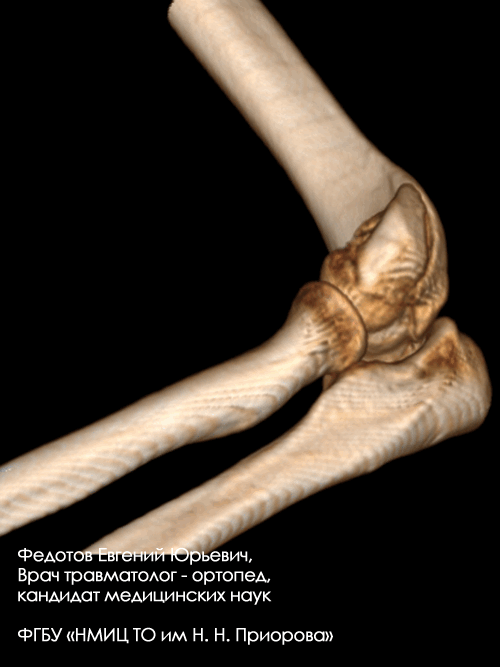

Пациентка с чрезвычайно тяжелым повреждением: тяжелым внутрисуставным переломом нижнего отдела плечевой кости с повреждением локтевого сустава с перелом средней трети локтевой кости со смещением отломков (дорожная травма).

Рентгенограмма до операции.

Выполнена операция: металлоостеосинтез плечевой кости пластинами LCP, анатомия локтевого сустава полностью восстановлена, остеосинтез локтевой кости стержнем с блокированием через небольшие разрезы-проколы (до 1 см.).

Гипсовая повязка после операции не применялась, сразу разрешена разработка движений в суставах конечности. Результат через 3 недели после операции. Уже видна хорошая функция конечности.

Результат через 4 мес. после операции. Функция конечности полностью восстановлена. Конечность ничем не отличается от здоровой.

Закрытый внутрисуставной перелом головочки, блока мыщелка и наружного надмыщелка плечевой кости со смещением.

Операция: открытая репозиция отломков дистального мыщелка плечевой кости, наружного надмыщелка, остеосинтез пластиной и винтами.

Закрытый внутрисуставной перелом головочки и части блока плечевой кости со смещением.

Операция: открытая репозиция отломков головочки и части блока плечевой кости, остеосинтез винтами.